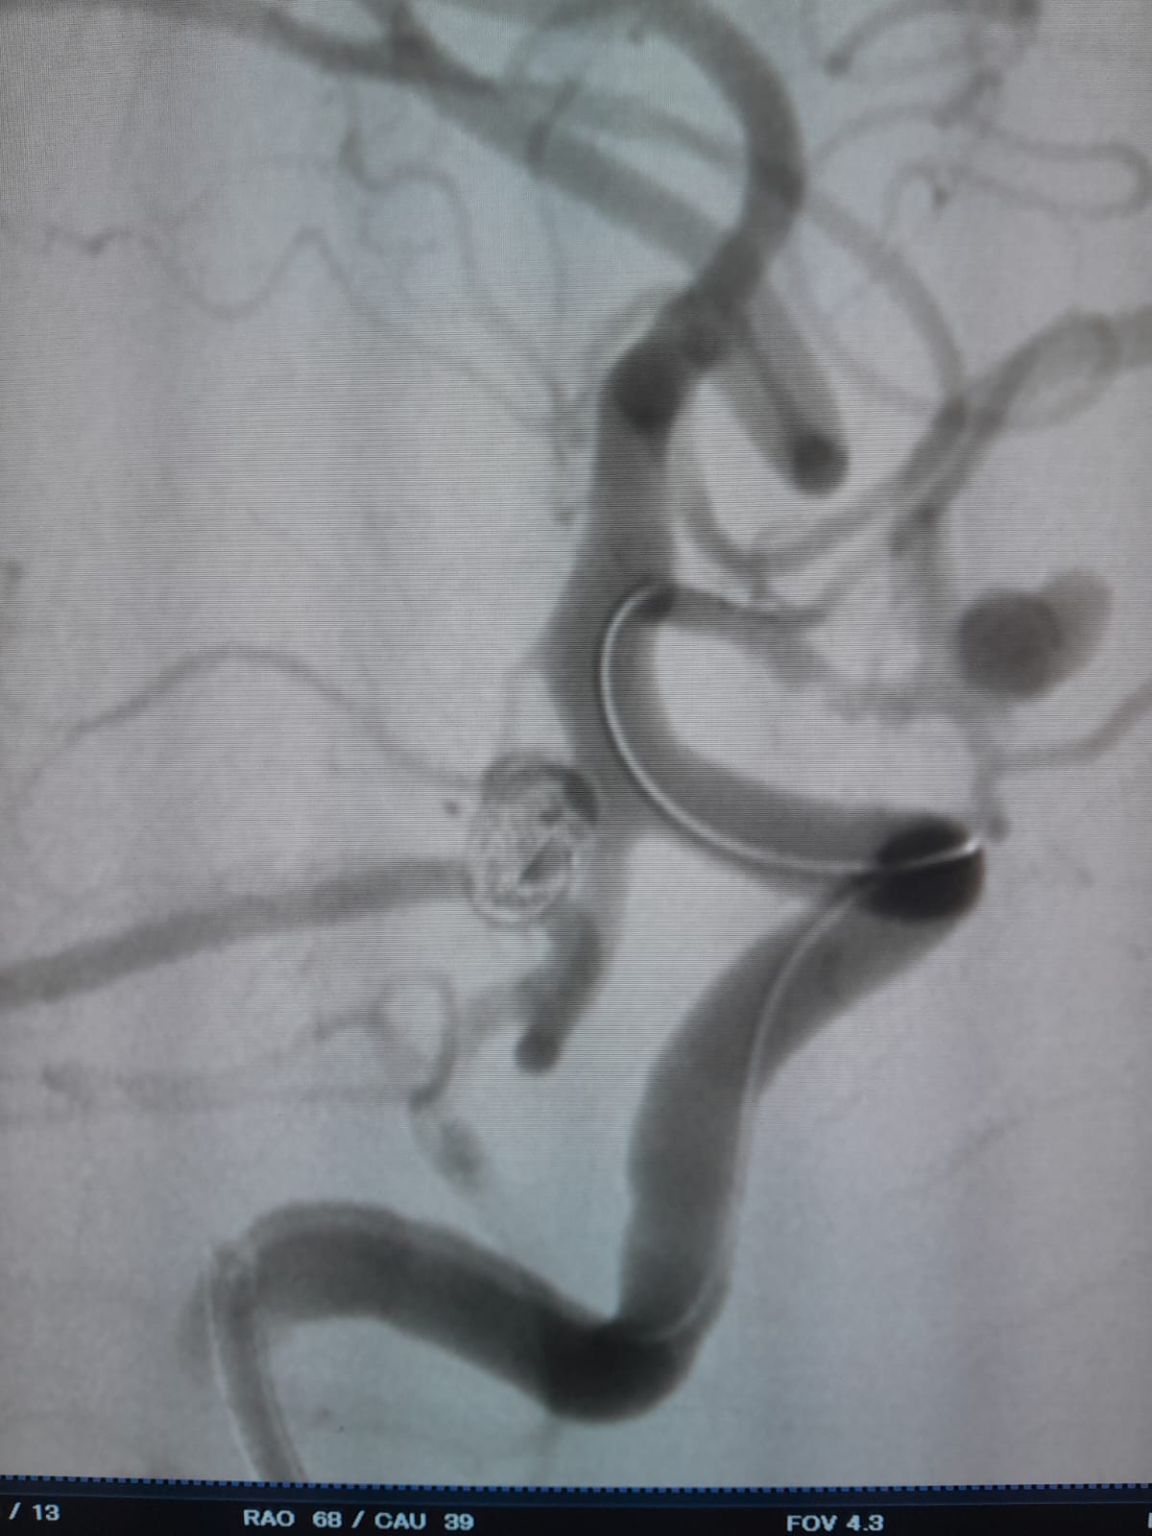

El paciente fue diagnosticado con un aneurisma de la arteria comunicante anterior (AComA) recién descubierto y un aneurisma de la arteria comunicante posterior (PComA) que había sido tratado previamente con embolización con espiral. Las imágenes de seguimiento revelaron un relleno residual en el aneurisma PComA, que requirió una intervención adicional.

Aneurisma de la arteria comunicante posterior (re-tratamiento)

Durante el seguimiento, se observó llenado residual en el aneurisma de la arteria comunicante posterior tratado previamente. El equipo reingresó al sitio usando el sistema de acceso a través de la aplicación de la tarjeta de crédito®Microcatéter desechable (TJMC18 Plus) e implementado con éxito un Nuva®Desviador del flujo (TJED-D-4.5-16), que demostró aposición ideal de la pared y desviación excelente del flujo, llevando a los resultados altamente satisfactorios del tratamiento.